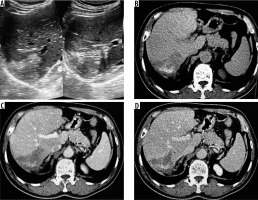

Ultrasonography revealed features of ill-defined, heterogeneously hyper-echoic hepatic mass lesion with no detectable calcification in 12 cases (52%) (Figure 1). Eight patients (34.7%) showed ill-defined hyperechoic hepatic mass with scattered foci of calcification (Figure 2). Two patients showed complex hepatic mass with heterogeneous solid component and associated cystic areas. And one patient showed thick-walled cystic lesion with calcifications in the wall.

Figure 1

A) Transverse ultrasound image of liver shows a peripheral wedge-shaped hyperechoic mass in segment VII. B) Non-contrast axial computed tomography (CT) image shows wedge-shaped hypodense mass with central calcifications. Post-contrast axial CT image in portal phase (C) and hepatic venous phase (D) does not reveal any enhancement of the lesion. No biliary dilatation or vascular invasion is seen (P1 disease)

A) Transverse sonogram of liver shows a large heterogeneously hyperechoic mass with central foci of calcification (arrow). B) Axial non-contrast computed tomography (CT) image shows hypodense mass with central calcification (arrow). Post-contrast axial CT images (C, D) do not reveal any enhancement of the mass. There is left lobe biliary dilatation (P2 disease)

On non-contrast CT, 15 patients (65%) revealed hypodense hepatic mass with scattered foci of calcification with no associated cystic component (Figures 1 and 2). Four (17.3%) patients revealed complex hepatic mass with hypoattenuating cystic areas and hyperattenuating calcifications (Figure 3). Four (17.3%) patients revealed thick walled hypodense cystic lesion (Figure 4). None of the lesions showed intralesional enhancement in arterial, portal, or hepatic venous phase CT (Figures 1 and 2). Five cases showed mild peripheral irregular enhancement in hepatic venous phase. Hepatic atrophy with capsular retraction was seen in three cases. One patient had superadded infection with hepatic abscess formation that required pigtail catheter drainage. With regards to the extent of disease, seven patients showed peripheral hepatic lesions with no biliary or vascular involvement (P1). Biliary radical obstruction was seen in seven patients. Peripheral biliary radicals above the primary confluence were infiltrated in four (P2). Hepatic hilar involvement with both lobe biliary radical dilatation was seen in three patients (P3). Single hepatic vein involvement was seen in three patients (P2). Three patients showed combined infiltration of at least two hepatic veins (P3). Main portal vein encasement was seen in two patients, and two showed combined infiltration of both IVC and hepatic veins (P4) (Figure 5). Extra hepatic infiltration was seen in four cases including adrenal gland infiltration in two patients, parietal wall infiltration in one patient, and diaphragmatic invasion in one patient (Figure 6) (N1 disease). Three patients showed metastatic disease. Two among them had pulmonary involvement (Figure 6) and one had splenic involvement (M1 disease). A break up of the patients according to PNM staging is given in Table 2. On MRI all the patients showed hypointense signal intensity on T1-weighted sequence. On T2-weighted sequence one (5.2%) patient showed micro-vesicular cysts with no solid component (Kodama type 1) (Figure 3C). Six (31.5%) patients showed heterogeneous signal intensity mass with both hypointense solid and hyperintense cystic components (Kodama type 2) (Figure 3D). Two (10.5%) patients showed central hyperintense cystic component with surrounding hypointense solid component (Kodama type 3). Eight (42.1%) patients showed hypointense mass with no cystic component (Kodama type 4) (Figure 7). Two patients (10.5%) showed thick walled cystic lesions (Kodama type 5) (Table 3). Post-contrast T1-weighted images revealed no enhancement of the lesion. Three cases showed peripheral rim of enhancement in delayed phase. DWI revealed free diffusion characterised by low signal intensity on high b value DWI images and high signal on ADC in all cases (Figure 8) except one patient who had developed superadded infection with abscess formation and required pigtail drainage. Mean ADC value of HAE was 1.74 ± 0.48 × 10-3 mm2/s (range: 1.39 × 10-3 mm2/s to 2.3 × 10-3 mm2/s). Mean ADC of different Kodama types of HAE did not differ significantly from each other (p = 0.058) (Table 3). The mean ADC of the surrounding liver parenchyma was 1.10 ± 0.21 × 10-3 mm2/s.